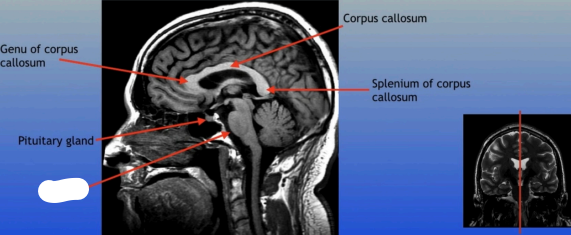

Genu of Corpus Callosum

The anterior part of the corpus callosum that connects the frontal lobes of the left and right hemispheres, playing a role in interhemispheric communication.

Pituitary Gland

A small pea-sized gland located at the base of the brain, often referred to as the "master gland" because it regulates many bodily functions through hormone secretion.

Corpus Callosum

Splenium of Corpus Callosum